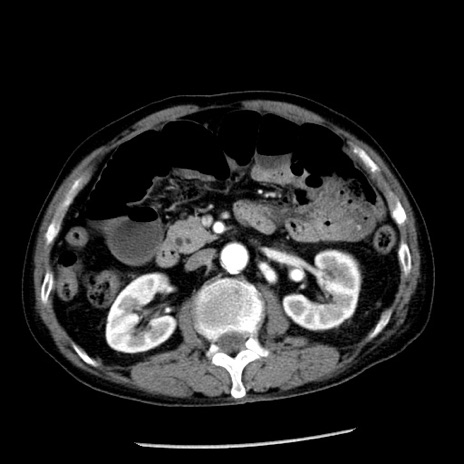

症例26(横断像)

【症例】80歳代男性

【主訴】嘔吐

【現病歴】昨晩2回嘔吐あり、今朝になっても嘔吐あり。来院。

【既往歴】胃潰瘍

【身体所見】意識清明、BT 37.6℃、BP 166/95mmHg、HR 100bpm、SpO2 97%、腹部:平坦・軟、腸蠕動音聴取良好、圧痛なし。

【データ】WBC 21900、CRP 1.46